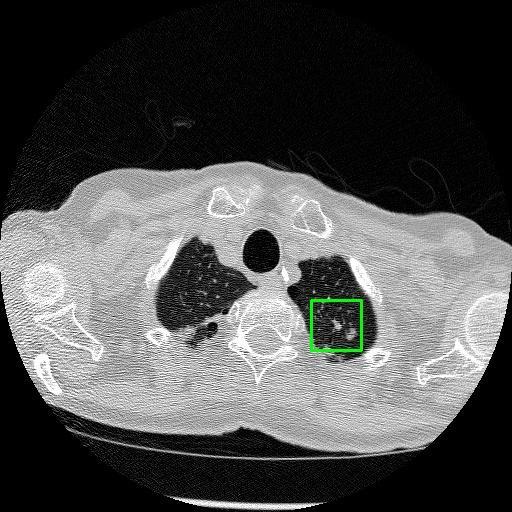

We developed an AI-based system using deep learning models for analyzing lung CT scans to detect and classify pulmonary nodules. We chose the YOLOv11 architecture for its enhanced object detection capability and adapted it specifically for medical imaging, incorporating pixel-level precision and severity classification.

Classification into three severity levels with colored bounding boxes.

Successfully built and deployed an AI model (YOLOv11) capable of detecting lung nodules in CT scans with high accuracy and real-time performance.

Designed a severity classification system that categorizes nodules into null, moderate, and severe using colored bounding boxes, assisting in rapid clinical decision-making.